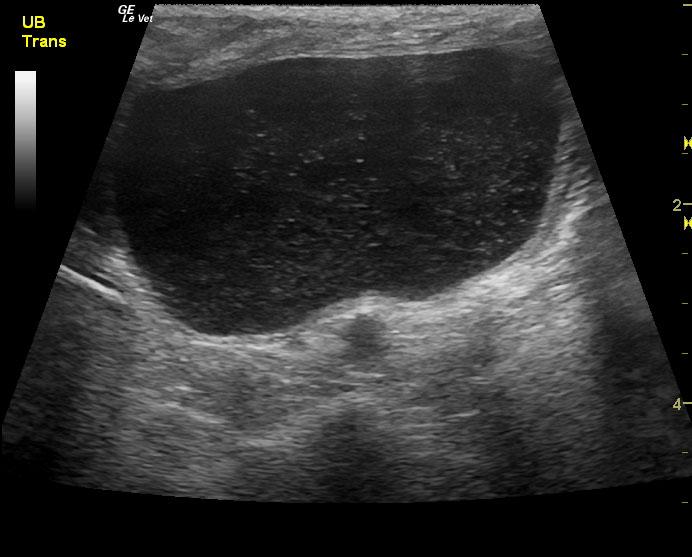

A 14-year-old neutered male Pomeranian dog was presented for evaluation of pollakiuria, diarrhea, inappetence, and lethargy. Abnormalities on physical examination included a painful, enlarged and symmetrical prostate, a very large and firm urinary bladder that could be expressed, and a grade III/VI heart murmur. On survey thoracic radiographs, calcification of the prostate gland was evident.

A 14-year-old neutered male Pomeranian dog was presented for evaluation of pollakiuria, diarrhea, inappetence, and lethargy. Abnormalities on physical examination included a painful, enlarged and symmetrical prostate, a very large and firm urinary bladder that could be expressed, and a grade III/VI heart murmur. On survey thoracic radiographs, calcification of the prostate gland was evident.